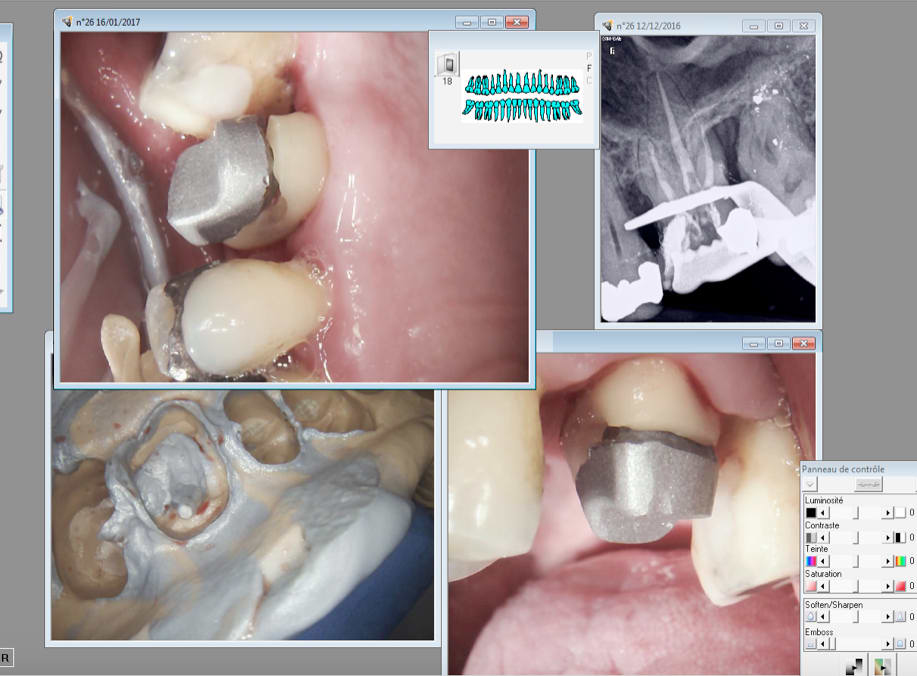

Ah bon, il m'a expliqué quelque chose? Il s'est étonné de la taille de la prémo et je lui ai expliqué pourquoi je l'avais faite de cette taille... En même temps, il ne pouvait pas deviner, la 35 n'apparait pas sur les documents postés, ou très peu sur une photo je crois...